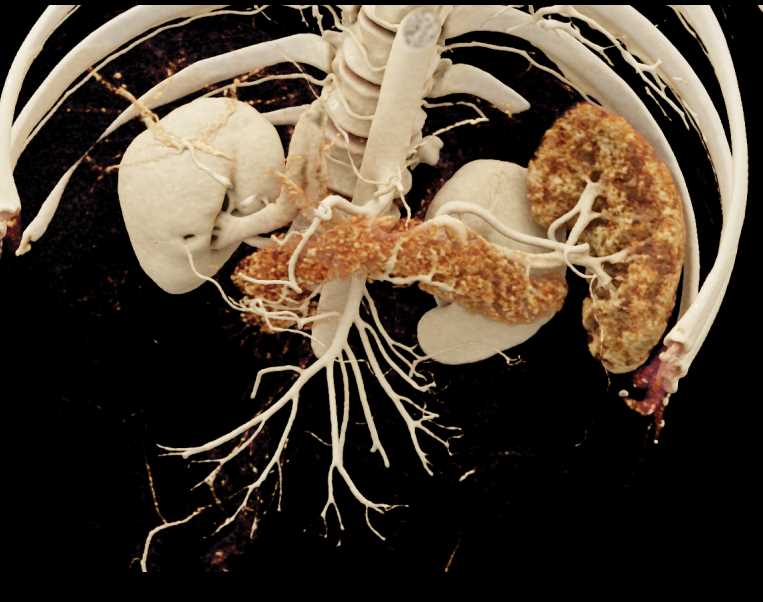

Subtle Neuroendocrine Tumor Body of Pancreas